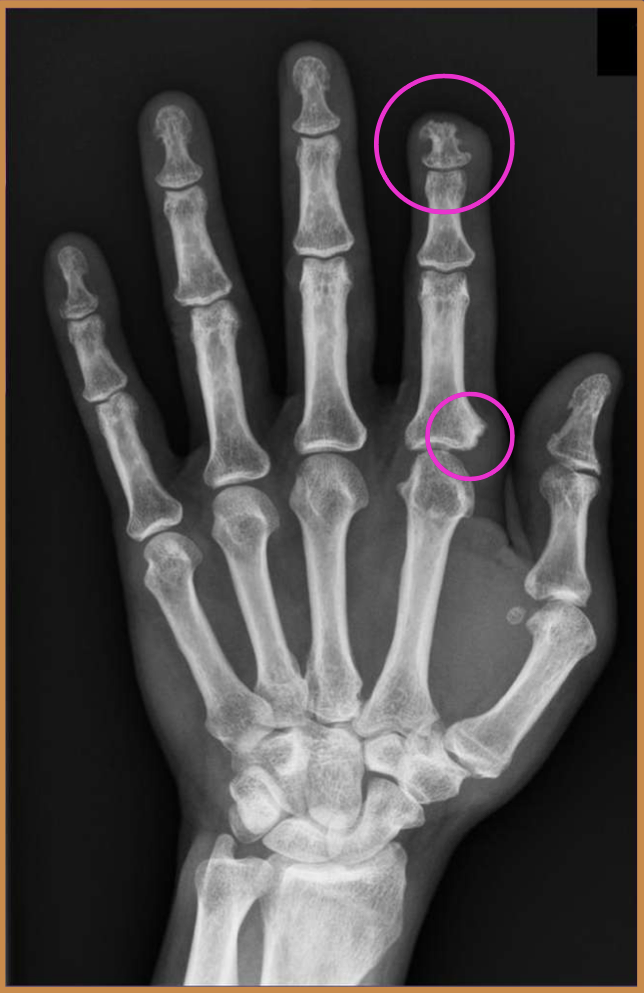

What two findings of PsA are found in this image

periostitis (mouse ears) - lifts periosteum

soft tissue edema - leaves bone density alone

How are the erosions mentioned in the question beforehand different from RA

In RA… don’t lift periosteum, decrease bone density, goes wherever it wants

What finding of PsA is found in this image

central lesions (pencil in cup)

What type of characterisitcs of PsA are found in this image

soft tissue edema

nail pitting

JSN + central erosions (pencil in cup)

periostitis (lifted periosteum - mouse ears)